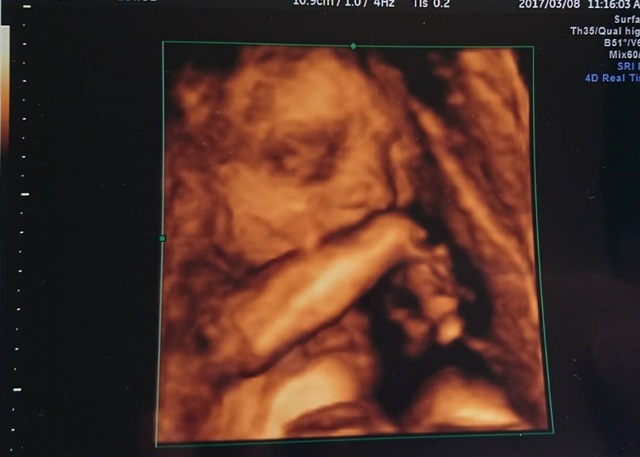

28週0日(28w0d・男の子)|ゆうきち0114 さん(28歳)

エコー写真撮影時のエピソード:

毎月の検診で顔が見れる!といつも楽しみでのぞむのですが…いつも手で顔を隠していて顔が見れずじまいでした。

この時初めて我が子の顔が写った!!と思いきや、なんだか鼻をほじってるようにも見え、なんだかクスッとなるような我が子との対面になりました。